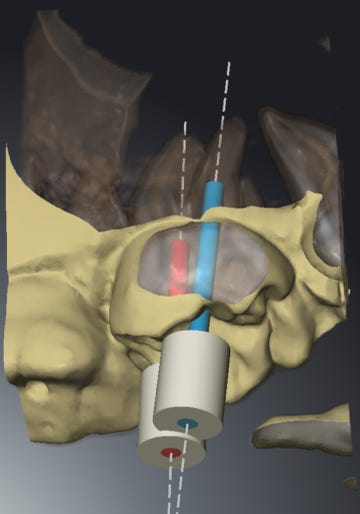

Methodological development and experimental testing of guided endodontic treatment support by using combined 3D imaging and computer aided guidance followed by clinical testing. This research was implemented into the SICAT Endo software and SICAT Access guide support.